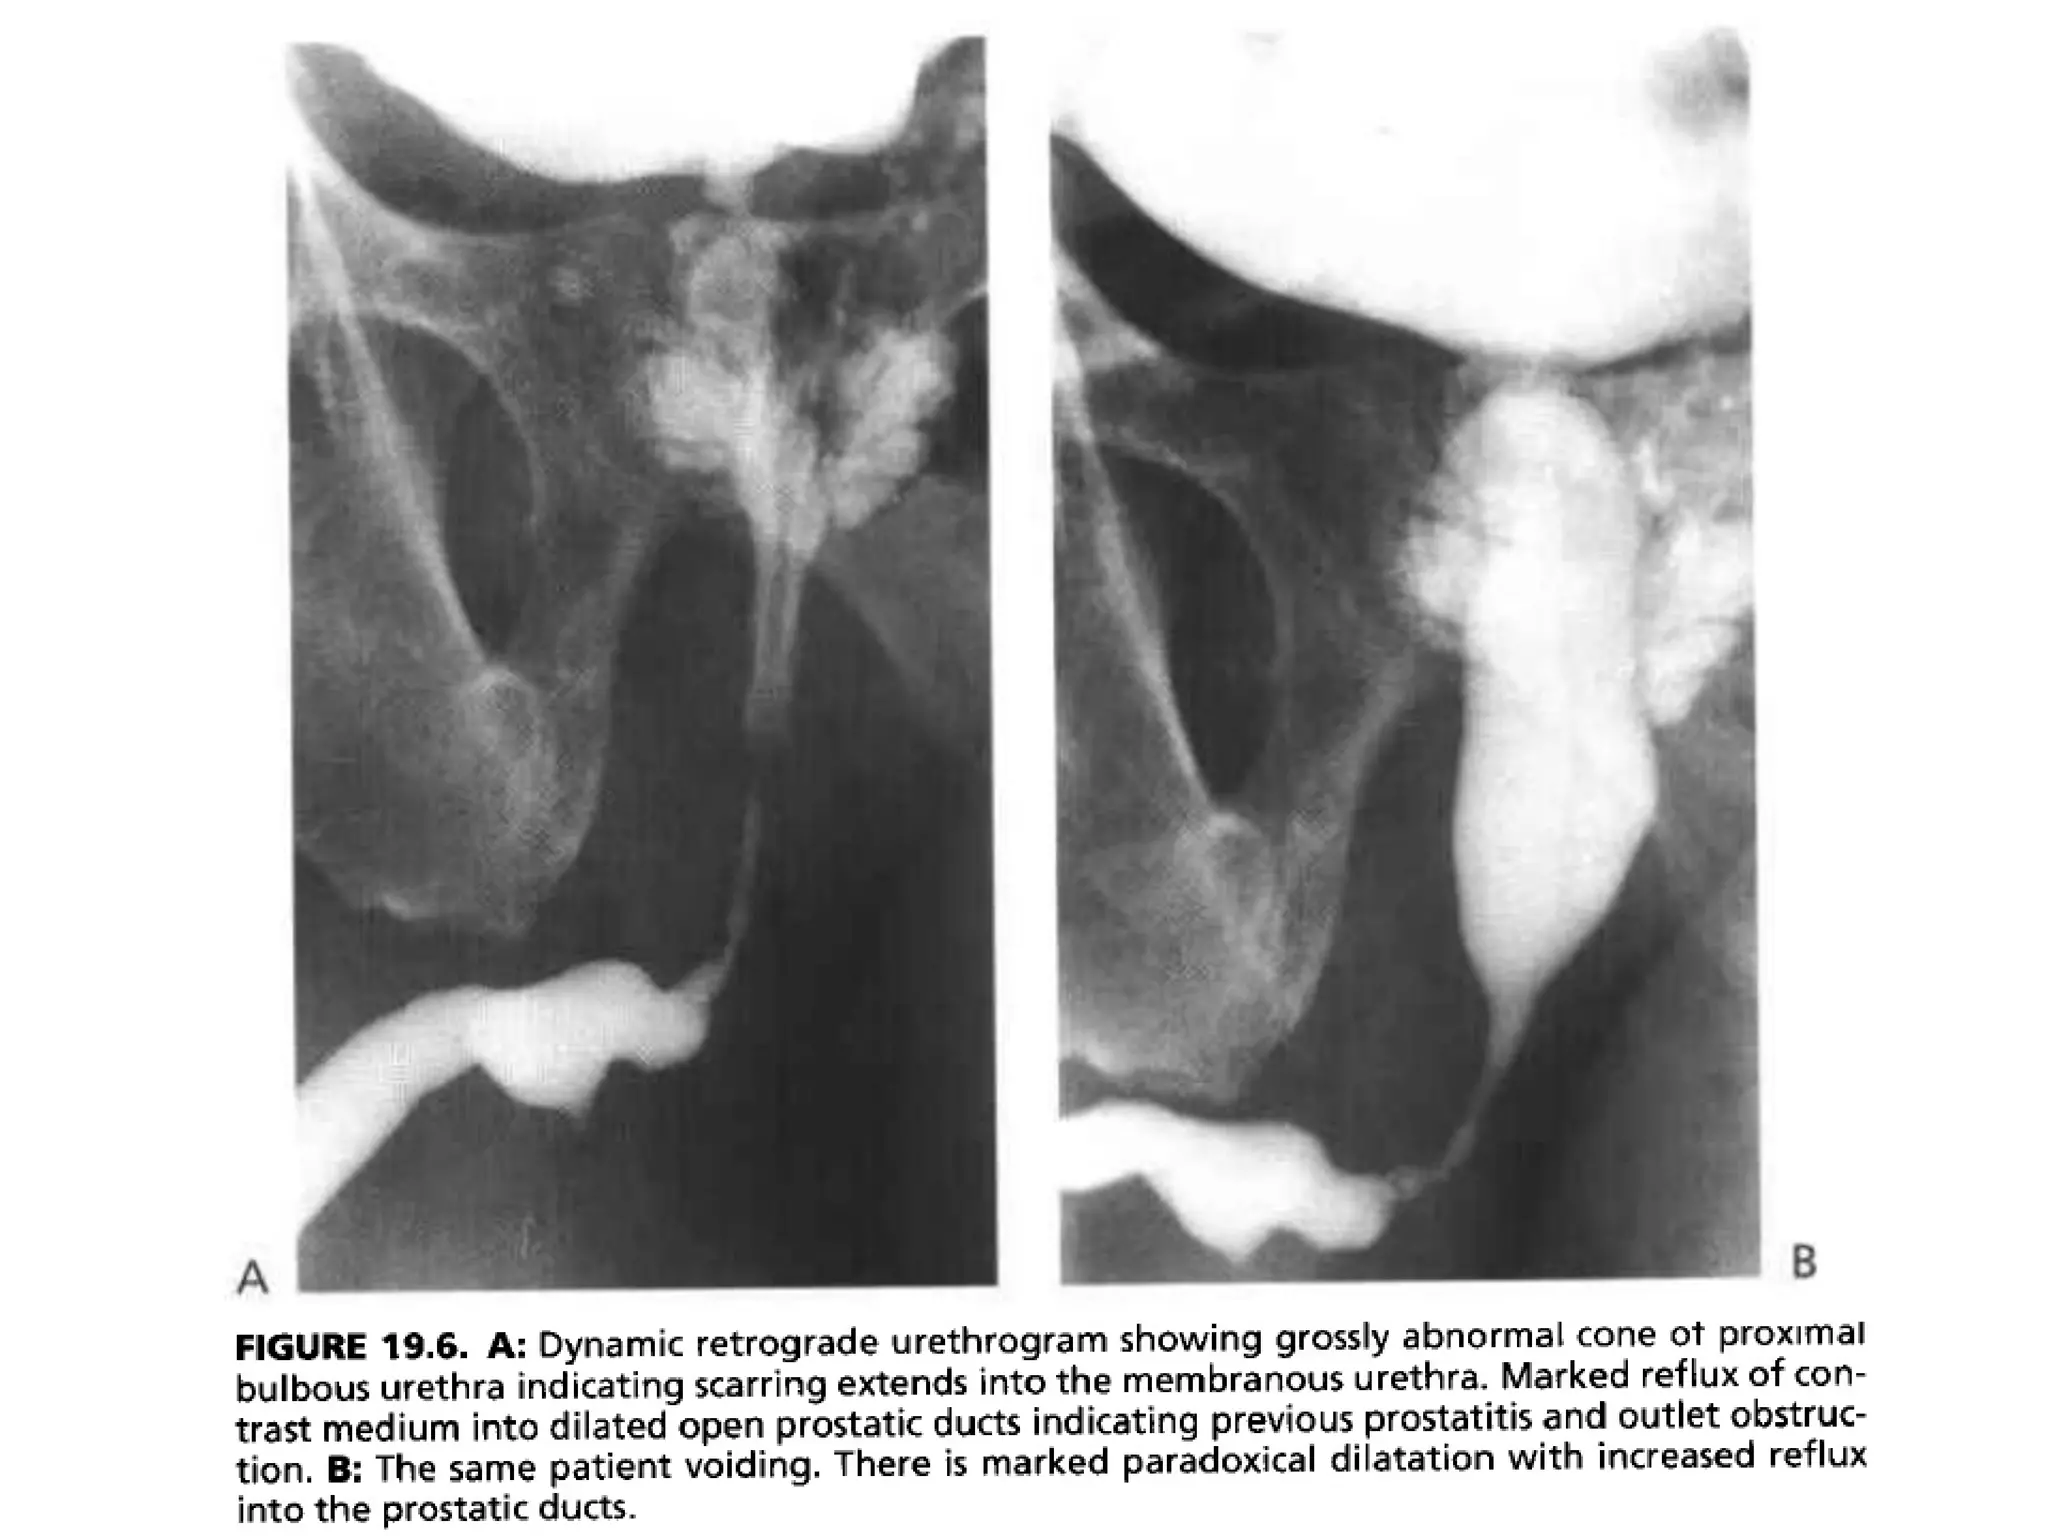

• If the disease has spread proximaly to the

membranous urethra, the normal cone shape of

the proximal bulbous urethra becomes

asymmetric and narrowed, giving an elongated

appearance to the membranous urethra.

• Abnormality of the normal convex cone shape of

the proximal bulbous urethra indicates scarring

extending into the membranous urethra.

• This radiologic finding is of prime importance to

the urologist, because surgical treatment may

involve cutting the scar tissue and consequently

the distal sphincter, which can result in iatrogenic

incontinence.

• High intraurethral pressure proximal to a stricture

not only results in dilation of the urethra, but also

can cause reflux of urine into the prostatic ducts.

• Ostia for these ducts, 30 to 40 in number, are

found in the floor of the prostatic urethra around

the verumontanum.

• This reflux may be massive and may allow

infection to enter the prostate, potentially

resulting in a prostatic abscess or formation of

multiple prostatic calculi.